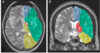

Label 5, 6 & 7

1 - superior temporal gyrus;

2 - inferior frontal gyrus; 3 - insular cortex;

4 - temporal stem;

5 - internal capsule;

6 - thalamus;

7 - lentiform nucleus (the internal and external globus pallidus and the putamen)

8 - frontal horn;

9 - superior circular sulcus;

10 - inferior circular sulcus.

Q

What type of posturing is this person displaying? [1]